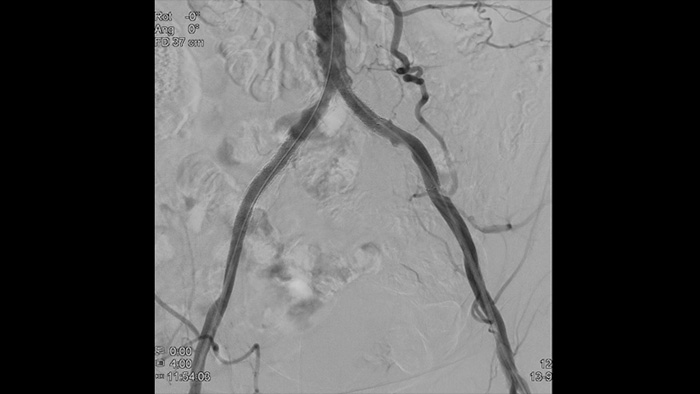

Images de haute définition de vaisseaux avec une vascularité très détaillée pour prendre en charge des stratégies de traitement, une navigation et un suivi de la plus grande précision.

Voyez clairement, traitez de manière optimale La gamme d’appareils Philips offre aux médecins la possibilité de visualiser clairement et de traiter de manière optimale.